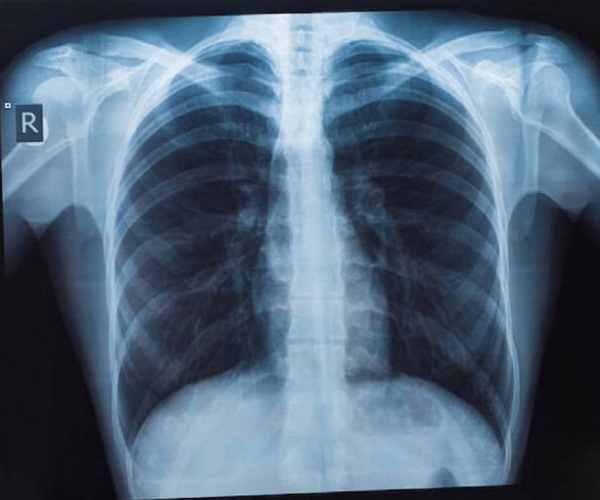

รศ.นพ.ศิระ เลาหทัย ศัลยแพทย์ทรวงอกจากศูนย์ผ่าตัดส่องกล้อง โรงพยาบาลวชิรพยาบาล กล่าวว่า มีคำถามยอดฮิตที่ว่า “เจอจุดที่ปอด (lung nodule) มีโอกาสเป็นมะเร็งกี่เปอร์เซ็นต์?” นั้นหลายครั้งที่เราไปตรวจสุขภาพแล้วพบเจอฝ้าขาว เมื่ออ่านผลรังสีวินิจฉัยพบเจอความผิดปกติในฟิล์มเอกซเรย์ปอด ทั้ง ๆ ที่เรายังไม่มีอาการผิดปกติใด ๆ เลย สิ่งที่สำคัญที่สุด ก็คืออย่าเพิ่งตกใจเราต้องหาสาเหตุของจุดที่เกิดขึ้นมีจริงหรือไม่ โดยวิธีการที่หาสาเหตุที่ดีที่สุดคือการทำเอกซเรย์คอมพิวเตอร์(CT scan) แต่ไม่ควรที่จะทำเอกซเรย์ซ้ำ เพราะไม่เกิดประโยชน์ เนื่องจากการทำฟิล์มเปรียบเสมือนการถ่ายภาพ 2 มิติ เห็นแค่ด้านหน้า-หลัง ส่งผลทำให้เกิดผลภาพลวงได้บ่อย เปรียบเทียบกับการทำเอกซเรย์คอมพิวเตอร์เห็นรายละเอียด เป็นลักษณะของก้อนเนื้อว่าสงสัยมะเร็ง

หรือไม่ รวมทั้งมีจริงหรือไม่ หากการทำเอกซเรย์คอมพิวเตอร์ CT scan ไม่มีจุดหรือไม่พบจุด บางที่สิ่งที่เราเห็นจากฟิล์ม คือเงาที่ซ้อนทับกัน เนื่องจากมุมภาพ กรณีนี้มั่นใจได้ ว่าไม่มีอะไร ใช้ชีวิตปกติ ติดตามตรวจสุขภาพประจำปี ในทางกลับกัน เมื่อใดหากเราได้ทำเอกซเรย์คอมพิวเตอร์แล้วเจอว่ามีจุดที่ปอดที่ปอดจริงๆ โดย สาเหตุอาจเกิดได้จาก 1) มะเร็ง (อาจจะเป็นมะเร็งปอดหรือมะเร็งจากที่อื่นกระจายมา), 2) วัณโรคและ 3) อย่างอื่น ๆ เช่น เนื้องอกธรรมดาของปอด หรือ ในช่องทรวงอก

ซึ่งปกติเมื่อทำเอกซเรย์คอมพิวเตอร์ (CT scan) มักจะเจอจุดโอกาสเป็นมะเร็งแค่ 1% แนะนำควรเจอแพทย์ที่มีความเชี่ยวชาญ เช่น หมอโรคปอดหรือหมอผ่าตัดปอด เพื่อจะดูความน่าจะเป็น หรือติดตามอย่างไรดี ในกรณีที่เรียกว่าแจ็คพอตแตก ก็คือเมื่อใดที่สงสัยว่าก้อนเนื้อ อาจจะเป็นเนื้อร้ายการเอาชิ้นเนื้อเป็นสิ่งที่สำคัญที่สุดโดยสามารถทำได้หลายวิธี เช่น การส่องกล้องผ่านหลอดลม (Bronchoscope)โดยการเจาะเอาชิ้นเนื้อโดยการทำเอกซเรย์คอมพิวเตอร์ (CT guide Biopsy) ผ่าตัด (Surgical biopsy) ดังนั้นแนะนำการทำเอกซเรย์คอมพิวเตอร์ปอด (CT scan) จึงเป็นการฉายรังสีเอ็กซ์ไปที่ส่วนของหน้าอกหรือปอด โดยภาพจากการฉายรังสีนั้นจะถูกบันทึกลงในแผ่นฟิล์มที่มีความละเอียดสูง ซึ่งแพทย์จะใช้ในการตรวจวินิจฉัยความสมบูรณ์ของอวัยวะภายใน ทั้งทรวงอก ปอด และโครงสร้างข้างเคียง อีกทั้ง ปัจจุบัน วิวัฒนาการเราสามารถทำ Low dose CT การเอกซเรย์คอมพิวเตอร์ใช้รังสีต่ำ จึงเป็นการตรวจอย่างหนึ่งที่นิยมใช้กันมาก ในการคัดกรองมะเร็งปอดเพราะเป็นการตรวจที่ง่ายและสามารถคัดกรองได้เบื้องต้น ไม่เป็นอันตรายเพราะใช้รังสีที่มีปริมาณน้อย โดยรูปแบบการทำงานของเครื่องเอกซเรย์ปอดจะใช้เพื่อให้ได้ภาพรังสีของภาพภายในปอดทั้งหมด ปัจจุบันประเทศไทยได้ทำ“การเอกซเรย์ปอด” เป็นเครื่องมือสำคัญในการวินิจฉัยระบบการทำงานอวัยวะภายในที่ผิดปกติ ไม่ว่าจะเป็นการตรวจเช็คตั้งแต่บริเวณอวัยวะส่วนทรวงอกจนไปถึงส่วนของโครงสร้างกระดูกที่ครอบคลุมบริเวณปอดและหัวใจ ซึ่งเป็นอวัยวะสำคัญในการดำเนินชีวิตของมนุษย์ ดังนั้นการตรวจเอกซเรย์ปอด (การตรวจเช็คอวัยวะภายในของบริเวณส่วนทรวงอกที่ประกอบไปด้วยโครงกระดูก ปอดและหัวใจเป็นหลัก และได้มีการพัฒนาให้ภาพฉายรังสีถูกสแกนเป็นระบบดิจิตอล ทำให้ผู้ป่วยได้รับการวินิจฉัยที่แม่นยำมากขึ้น